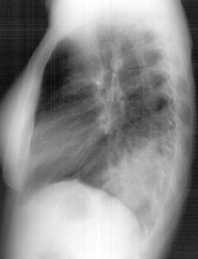

L’Rx del torace evidenzia un addensamento parenchimale che occupa la base di destra (Figure 1-2) con modesto versamento (ecografia: pochi millilitri). Indici di flogosi elevati (VES 52, PCR 17 mg/dL. GB 6.600, N73%, L11%, M15%, E1%, Plt 90.000). Emocultura negativa; ricerca di antigeni batterici nelle urine negativa, anticorpi anti-micoplasma <1/32; GOT 243, GPT 178, gammaGT 96.